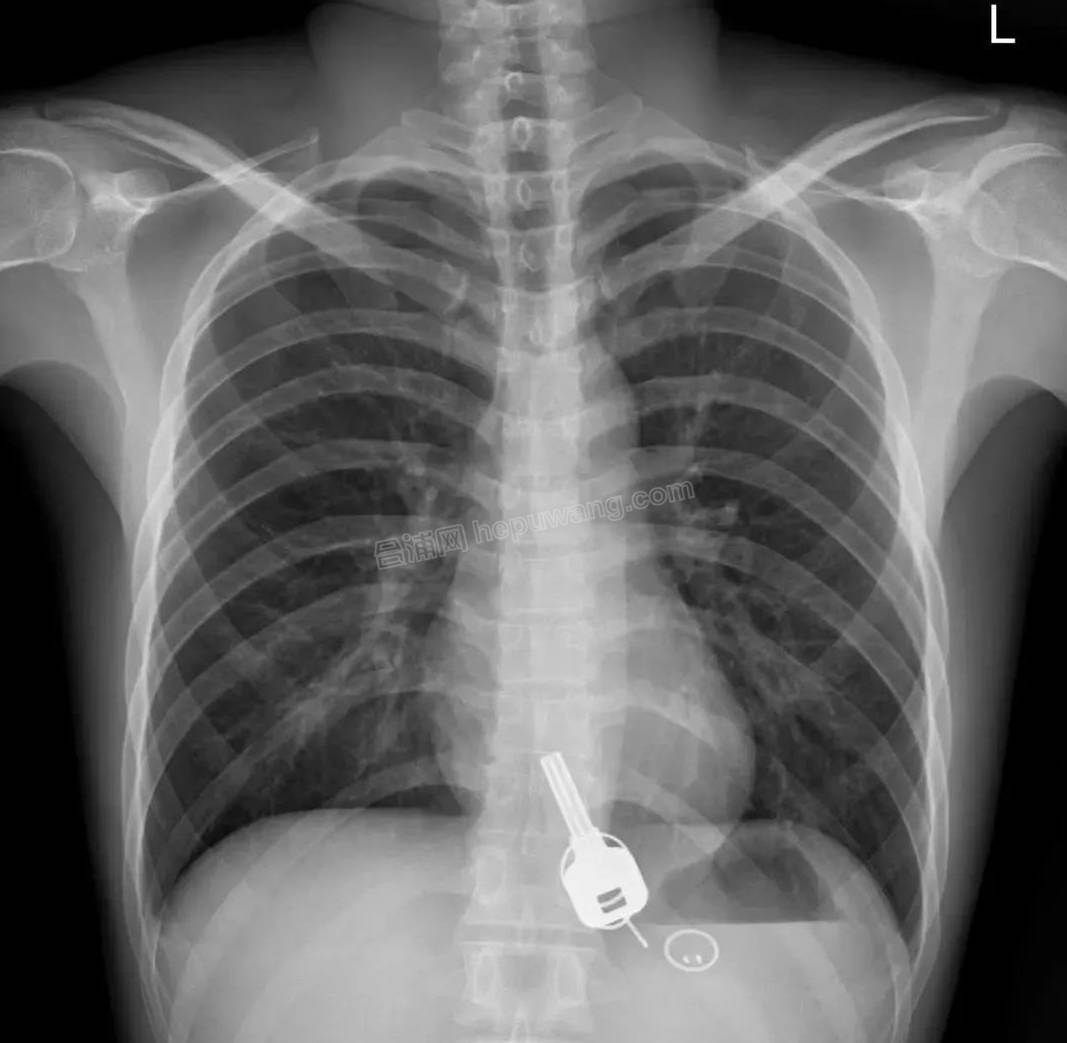

第二天一早,他来到东莞市人民医院急诊科就诊。结果吓一跳:他竟吞下了一把钥匙,钥匙上还有两个钥匙扣。

张镕宇让他拍个片子看看。拍X光的结果出来一看,常先生吓一跳,懵圈了:“什么回事?这,这……”

原来啊,拍片结果显示:在他肚子胃区的位置,有把铁钥匙、2个钥匙扣和1个门禁牌。那把钥匙正是他昨晚丢失找不见的。“我问他怎么回事?”6月9日上午,会诊医生张镕宇告诉记者,“当时,常先生回忆说,6月6日下班后,因考虑到第二天是端午假期,他约几个朋友一起吃饭喝酒,喝大了,之后什么都记不得。”

检查结果显示,钥匙在自己胃里。钥匙如何从他身上稀里糊涂跑到他胃里,常先生苦苦回忆,就是记不起来了。难题转到了医生那里。

疼痛科医生立即给患者做无痛胃镜,在麻醉情况下,患者食管入口处的肌肉会松弛,这样,在不用开刀的情况下,消化内科的医生终于还是顺利把钥匙取出来了。(来源:红星新闻)